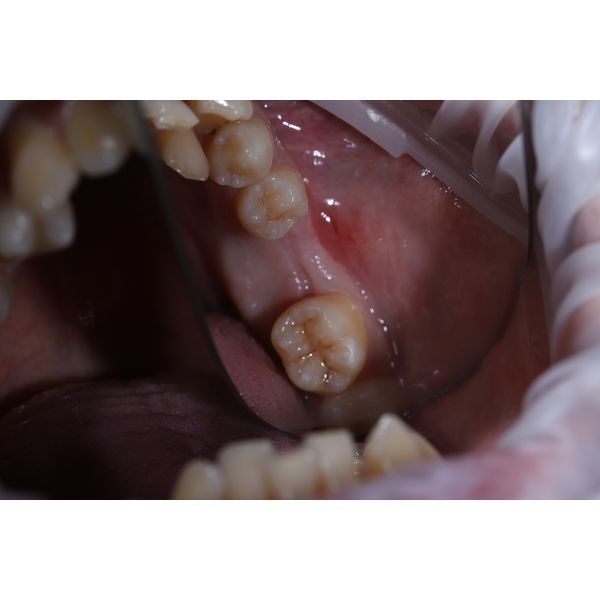

Слизистая оболочка рта бледно-розовая, умеренно увлажнена, без видимых патологических изменений. Прикус постоянный, перекрёстный. В центральном отделе нижнего зубного ряда отмечалась скученность зубов. Нижнего левого моляра не было, зубы 3.5 и 3.7 не соприкасались друг с другом. Альвеолярный гребень — вершина альвеолярного отростка, которая образуется после потери зуба — широкий, с пологим вестибулярным скатом. Костных новообразований не было.